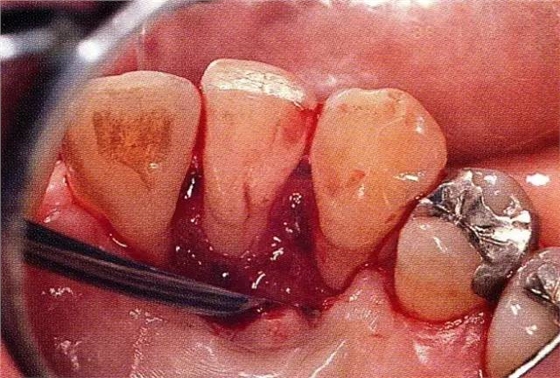

案例3針對(duì)3壁性垂直性骨缺損使用非吸收性膜進(jìn)行再生治療,再翻瓣時(shí)進(jìn)行骨形態(tài)修整的病例。

▲圖7-1左下6近中可觀察到3壁性垂直性骨缺損。此病例考慮到齦瓣供血關(guān)系,在前磨牙部位進(jìn)行了減張切開,沒有進(jìn)行縱切開。并利用刮治器、牙周外科用車針進(jìn)行了徹底的骨缺損部位搔刮。